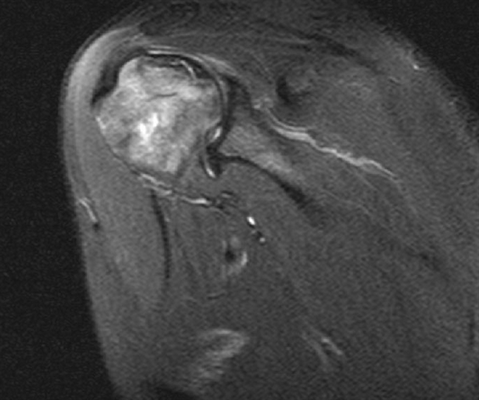

Пример МРТ заключения плечевого сустава

Плоскость сканирования: аксиальная, корональная, сагиттальная

Вид исследования: левый плечевой сустав

На серии МР томограмм взвешенных по Т1 и Т2 в трех проекциях получено изображение плечевого сустава. Контуры суставных поверхностей ровные, чёткие, не деформированы краевыми костными разрастаниями. Суставная щель не сужена, признаков подвывиха головки плечевой кости не выявлено. Мелкие кисты до 2-Змм в головке плечевой кости.

Фиброзно-хрящевая губа гленоида обычно расположена, форма её не изменена, целостность не нарушена.

Количество жидкости в полости плечевого сустава физиологическое. Небольшое количество жидкости в подклювовидной сумке. Определяется незначительное количество жидкости по ходу сухожилия длинной головки бицепса.

Субакромиальное расстояние - 6,5мм. Жидкости в подакромиальной сумке не определяется.

Дельтовидная мышца без особенностей.

Акромиально-ключичное сочленение - смежные поверхности акромиона и ключицы не деформированы.

Суставная ямка лопатки с ровными чёткими контрами, краевыми костными разрастаниями не деформирована. Гиалиновый хрящ не истончен.

Подклювовидный бурсит, незначительное количество жидкости по ходу сухожилия длинной головки бицепса.